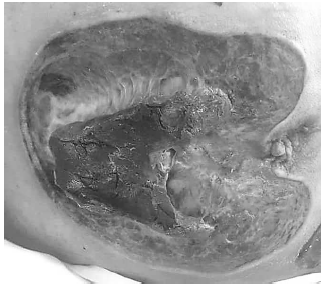

Paciente de 89 anos, com Doença de

Alzheimer avançada, totalmente acamado há 3 anos,

totalmente dependente para Atividades Básicas de

Vida diária, com múltiplas contraturas, necessidade de

uso de fralda por dupla incontinência, úlcera por

pressão sacral grau 4, com necessidade de uso de

Sonda Nasoentérica para alimentação por disfagia

grave e com afasia.

De acordo com a imagem, assinale a alternativa correta sobre como deve ser classificada a úlcera por pressão.